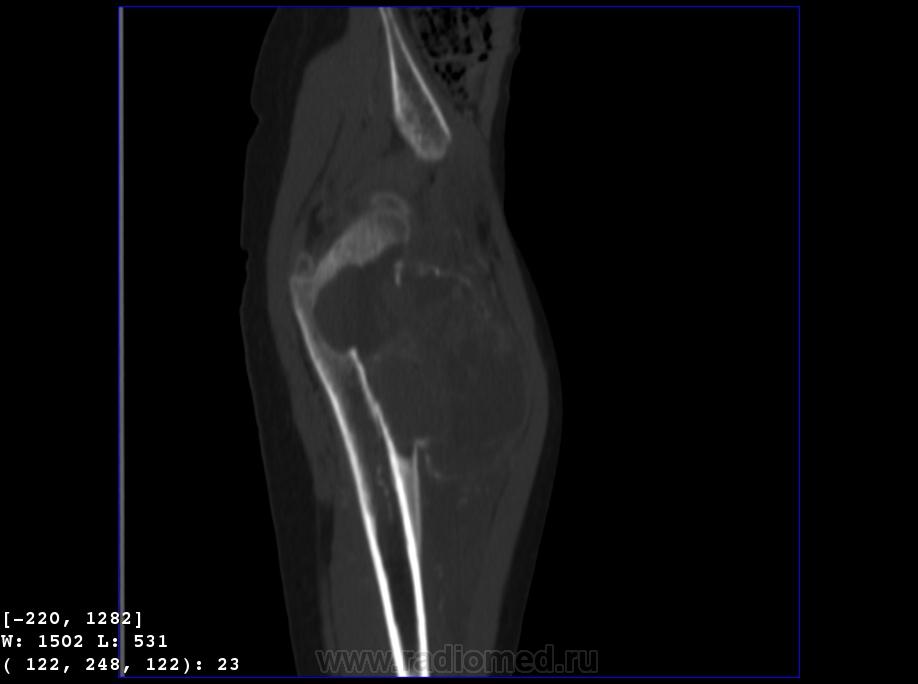

Девочка 9 лет. Родители отмечают, что 2 месяца назад девочка начала предъявлять жалобы на боли в правой пятке. Обследовались, патологии в стопе не нашли. Ребёнок постепенно начал хромать. А несколько дней назад обнаружили припухлость в в/3 бедра. Болей в бедре нет, как ночных, так и дневных. Температура не повышалась. Обратились за помощью - выполнены рентгенограммы, затем - КТ.

Злокачественная опухоль - виден луковичный периостит, инвазивный рост с лизисом кости. Но какая? Вроде бы растет из костного канала. Остеосаркома? Юинг? для этих опухолей структура какая-то больно хрящевая, мягкотканная. Хондросаркома? В таком возрасте? Почему нет клиники злокачественной опухоли кости, прежде всего - болей?

Коллеги, давайте правильно применять термины. Периостит - окончание воспаления, применяется при остеомиелите. При опухоли - периостоз - окончание избытка, продуктивного процесса. Здесь есть "козырек Кодмена", спикулообразный периостоз, но есть так же луковичный (слоистый) периостоз, который хорошо виден на отдельных КТ-срезах. Другое дело, что для диф. диагноза опухоли (то что процесс агрессивный - сомнений не вызывыает) это, по большому счету, ничего не дает. Однако, обратите внимание на вздутие. Считаю возможны варианты телеангиоэктатической или гигантоклеточной остеосаркомы. Так же не считаю возможным исключить саркому Юинга.

+ Не потому ,что не согласен с остальными,просто не хочется девчонке "зла " ,а ,кстати на аксиальном срезе -горизонтальные уровни есть ,или это мне кажется ?-Если есть -тогда может быть и впрямь АКК?

Вы правы, коллега, мне тоже видятся уровни. Но если АКК, откуда периостоз? По КТ его оспорить сложно... По скиалогии, локализации наиболее подходит гигантоклеточная опухоль, тем более, что она часто сочетается с вторичной аневризмальной кистой. Но возраст?! хотя, чего сейчас только не бывает...